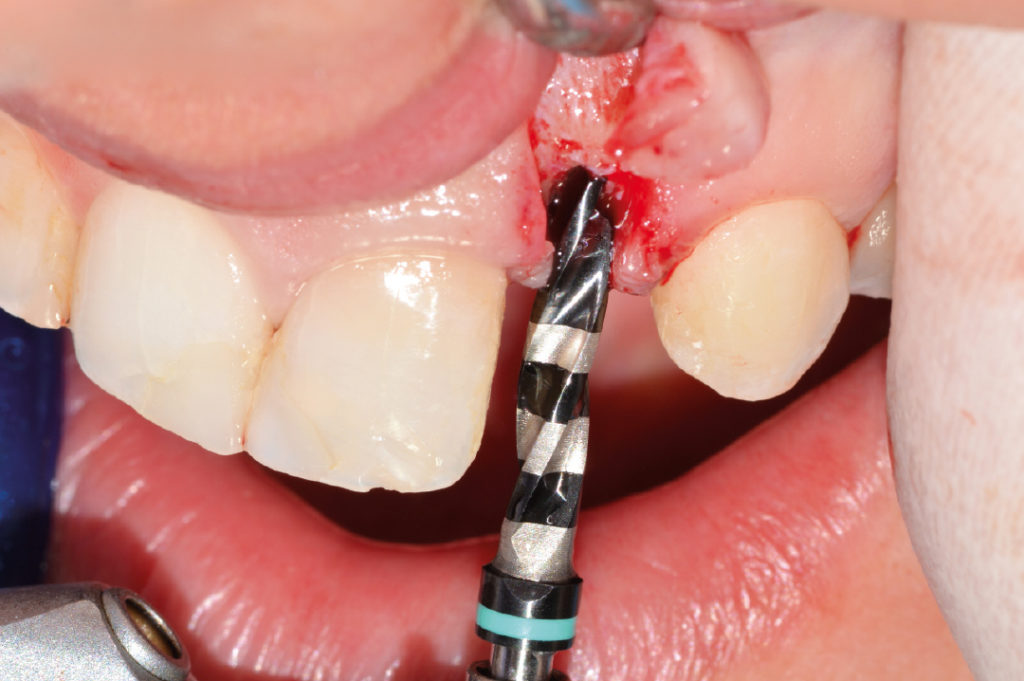

Use of 2.8 mm twist drill for about 6.5 mm

View of created osteotomy